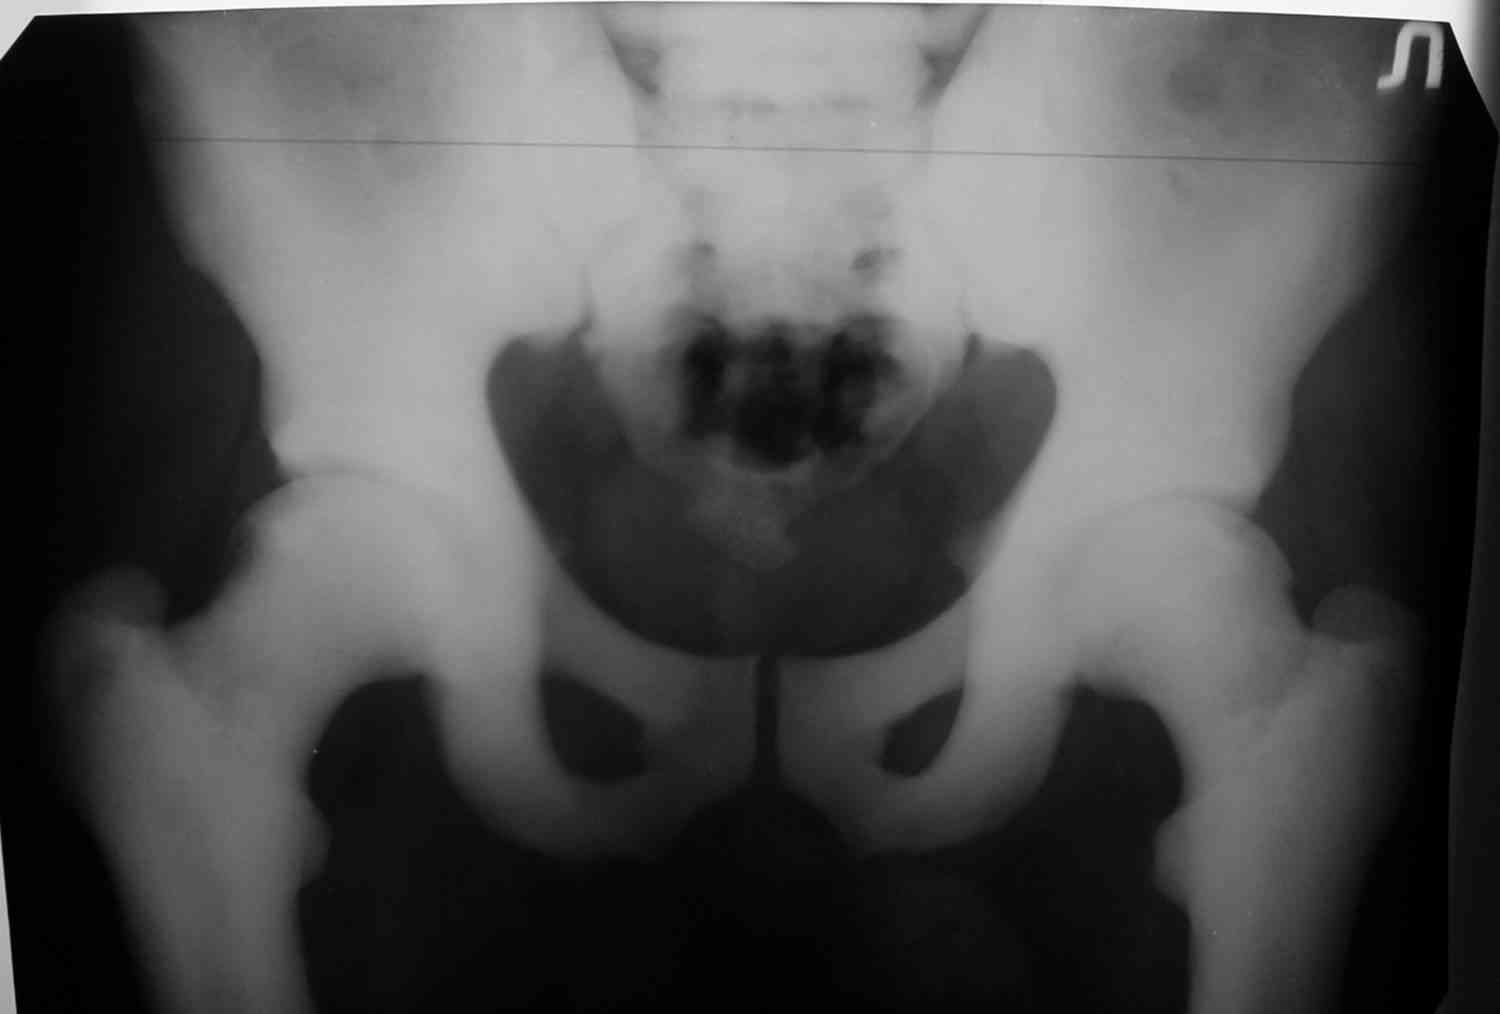

Уважаемый Константин Иванович! Полностью согласен с проф. Михайловым, данный случай не похож на мраморную болезнь, при которой имеется резкое, строго симметричное и генерализованное уплотнение костной ткани (остеопетроз), и кость оказывается построенной преимущественно из гомогенного компактного костного вещества. Для примера привожу случай из архива нашего института (бедренные, плечевые кости и таз, рис 1,2,3)

Изменения структуры костей у Вашего пациента больше похожи на полиоссальную форму фиброзной дисплазии или болезнь Педжета, возможены также инфаркты костного мозга б.берцовых костей. К сожалению, качество снимка не очень хорошее, непонятно, сохранен ли кортикальный слой б.берцовых костей по передней поверхности.